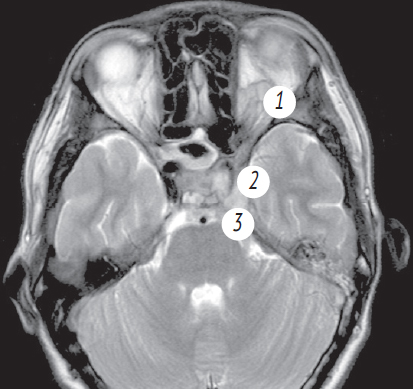

Риногенные внутричерепные осложнения, такие как абсцесс головного мозга и тромбоз вен и синусов головного мозга, по сей день остаются грозной, жизнеугрожающей патологией, не редко заканчивающейся летальным исходом, несмотря на широкое развитие антибактериальной терапии и приверженность пациентов к проводимому лечению. Нередко причиной развития внутричерепных осложнений служит обострение хронического воспалительного процесса в придаточных пазухах носа, тогда как острая ЛОР-патология синусов приводит к развитию риногенных осложнений лишь в небольшом проценте случаев. К сожалению, высокое развитие лучевой и лабораторной диагностики не всегда позволяет вовремя диагностировать данные состояния и оказать адекватную хирургическую помощь. В детском и подростковом возрасте важно выполнить своевременное полное и в то же время малоинвазивное, не приводящее к инвалидизации, хирургическое пособие. Анализ зарубежной литературы последних лет показывает, что нейрохирургические операции в различном объеме (от трепанопункции головного мозга до краниотомии) встречаются в подавляющем большинстве случаев лечения риногенных внутричерепных осложнений. В статье приводятся два клинических случая успешно пролеченных в отделении оториноларингологии Санкт-Петербургского государственного педиатрического медицинского университета пациентов с внутричерепными осложнениями без высокотравматичной нейрохирургической операции. Комбинация эндоназальной эндоскопической операции и массивной адекватной консервативной терапии (антибиотикотерапия в сочетании с применением антикоагулянтов при синус-тромбозе) позволяет добиться выздоровления пациента без обращения к нейрохирургическому вмешательству.